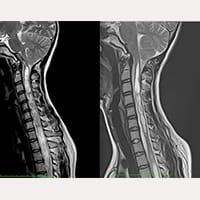

減壓手術後接受終絲手術病例